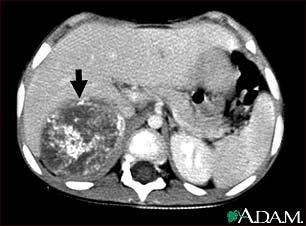

Neuroblastoma in the liver - CT scan

This CT scan of the upper abdomen shows a large tumor (neuroblastoma) on the person's right side (lower left side of picture). The tumor is behind the liver and is pushing the liver forward and may have possibly spread into the liver tissue.